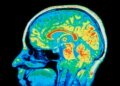

The “holes” that Kim Kardashian’s doctor said he saw on the reality…